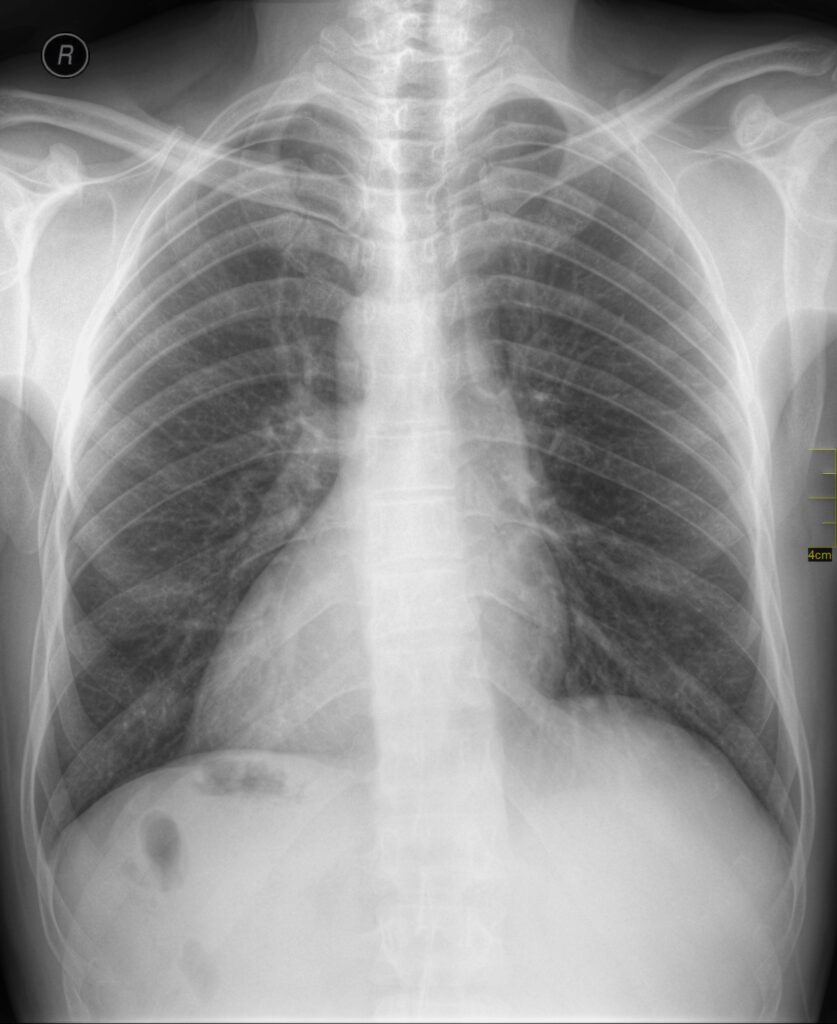

Na overleg met een cardioloog, wordt er besloten een thoraxfoto te vervaardigen. Ook dit zie je hieronder. Welke afwijking zie je daarop? Hoe hangt dit samen met het ECG?

Bespreking: we zien een staande X-thorax, vermoedelijk PA (posteroanterior) ingeschoten. Het mediastinum superius is slank. De hili zijn normaal. De hartcontour is afwijkend. Het hart bevindt zich in geheel abnormaal veel naar rechts in het mediastinum. Ook wijst de apex naar rechts, in plaats van naar links. Verder is de longvaattekening normaal, zien we geen pleurale effusie, geen verdichtingen in het longparenchym en geen afwijkingen aan het skelet. Als we naar de bovenbuik kijken, valt het ons op dat we luchtconfiguraties zien rechts subdiafragmaal (ter hoogte van waar we de lever zouden verwachten). Links subdiafragmaal zien we géén maagbubbel, maar juist dens weefsel (is dat de lever die aan de verkeerde kant zit)?.

Conclusie: dextrocardie (rechtszijdig hart), vermoedelijk met een situs inversus totalis

⚠️ Het komt wel eens voor dat een foto per abuis wordt gespiegeld bij de digitale verwerking! Verifieer dit dus altijd, voordat je bijzondere conclusies trekt.